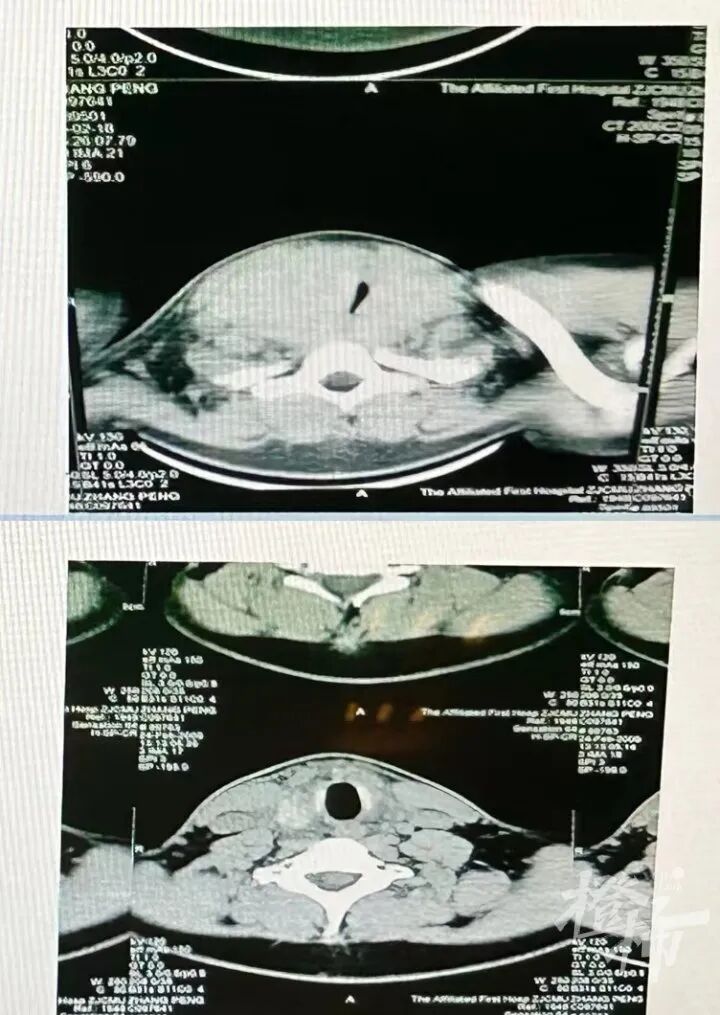

20岁的细雨也有雷同的履历,他比小玲的情形更严重,他来病院时吐气都很难题,睡觉时显现了严重的打呼声,甚至影响到了在近邻睡觉的怙恃。经由甲状腺B超搜检,细雨的气道被甲状腺肿瘤严重榨取。“原本通行的气道被榨取到只剩一道极窄的裂缝,所以他才会显现吐气难题、打呼严重的情形。”傅传授说。手术后,细雨终于恢复正常,可以顺畅吐气了。

细雨手术前后的气道对比图。(病院供图)